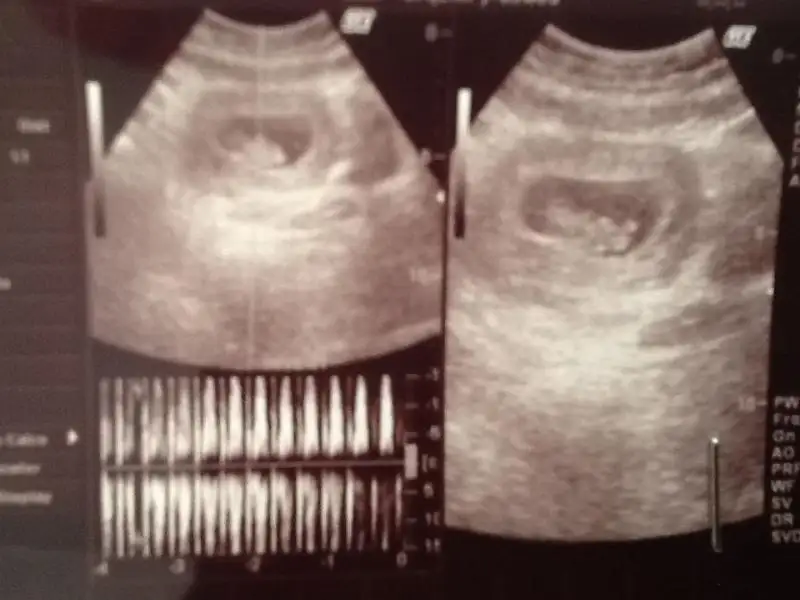

dr soylemeden siz gorun genital nub teorisi ( bebegin cinsiyeti)

Arkadaslar banada tahmınde bulunurmusunuz bebegım kızmı erkekmı cok merak edıyorum orkıde hanım lutfennn tahmınlerınızı beklıyorum